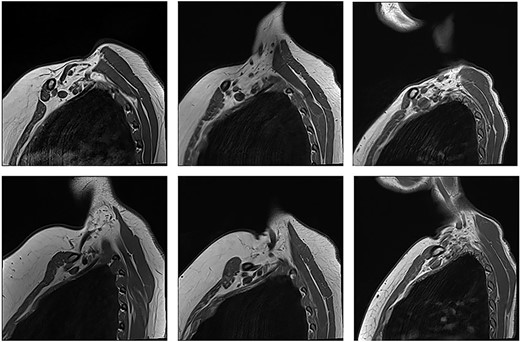

With the arm elevated, there is narrowing of the costoclavicular space between the posterior border of the clavicle and anterior border of the first rib (Figs 1 and 3). In unaffected patients, there is a small amount of fat that persists around the cords of the brachial plexus with the arm elevated (Fig. 2). In our series, we considered a patient to be positive for nTOS if there is loss of the perineural fat signal demonstrating that the nerves are in direct contact with the posterior border of the clavicle and anterior border of the first rib (Fig. 1b).

Panel a. Sagittal T1-weighted MRI of the costoclavicular space without imaging evidence of nTOS. Arm alongside the body (i) and arm elevated (ii). Maintenance of a fat plane surrounding the cords is seen with physiological narrowing of the space. Panel b. Sagittal T1-weighted MRI of the costoclavicular space with imaging evidence of nTOS. Arm alongside the body (i) and arm elevated (ii). Narrowing of the costoclavicular space and complete effacement of the fat indicating brachial plexus compression. Panel c. Venograms conducted with contrast injection in the antecubital vein while the arm is alongside (i) and in salute pose (ii) demonstrates tight stenosis of the subclavian vein and collateral flow. The MRI also showed effacement of the brachial plexus. The 36 year-old male subject had an excellent outcome after excision of the 1st rib. C: Clavicle; FR: First rib, SV: Subclavian vein, SA: Subclavian artery, LC: Lateral cord, MC: Medial cord, PC: Posterior cord.